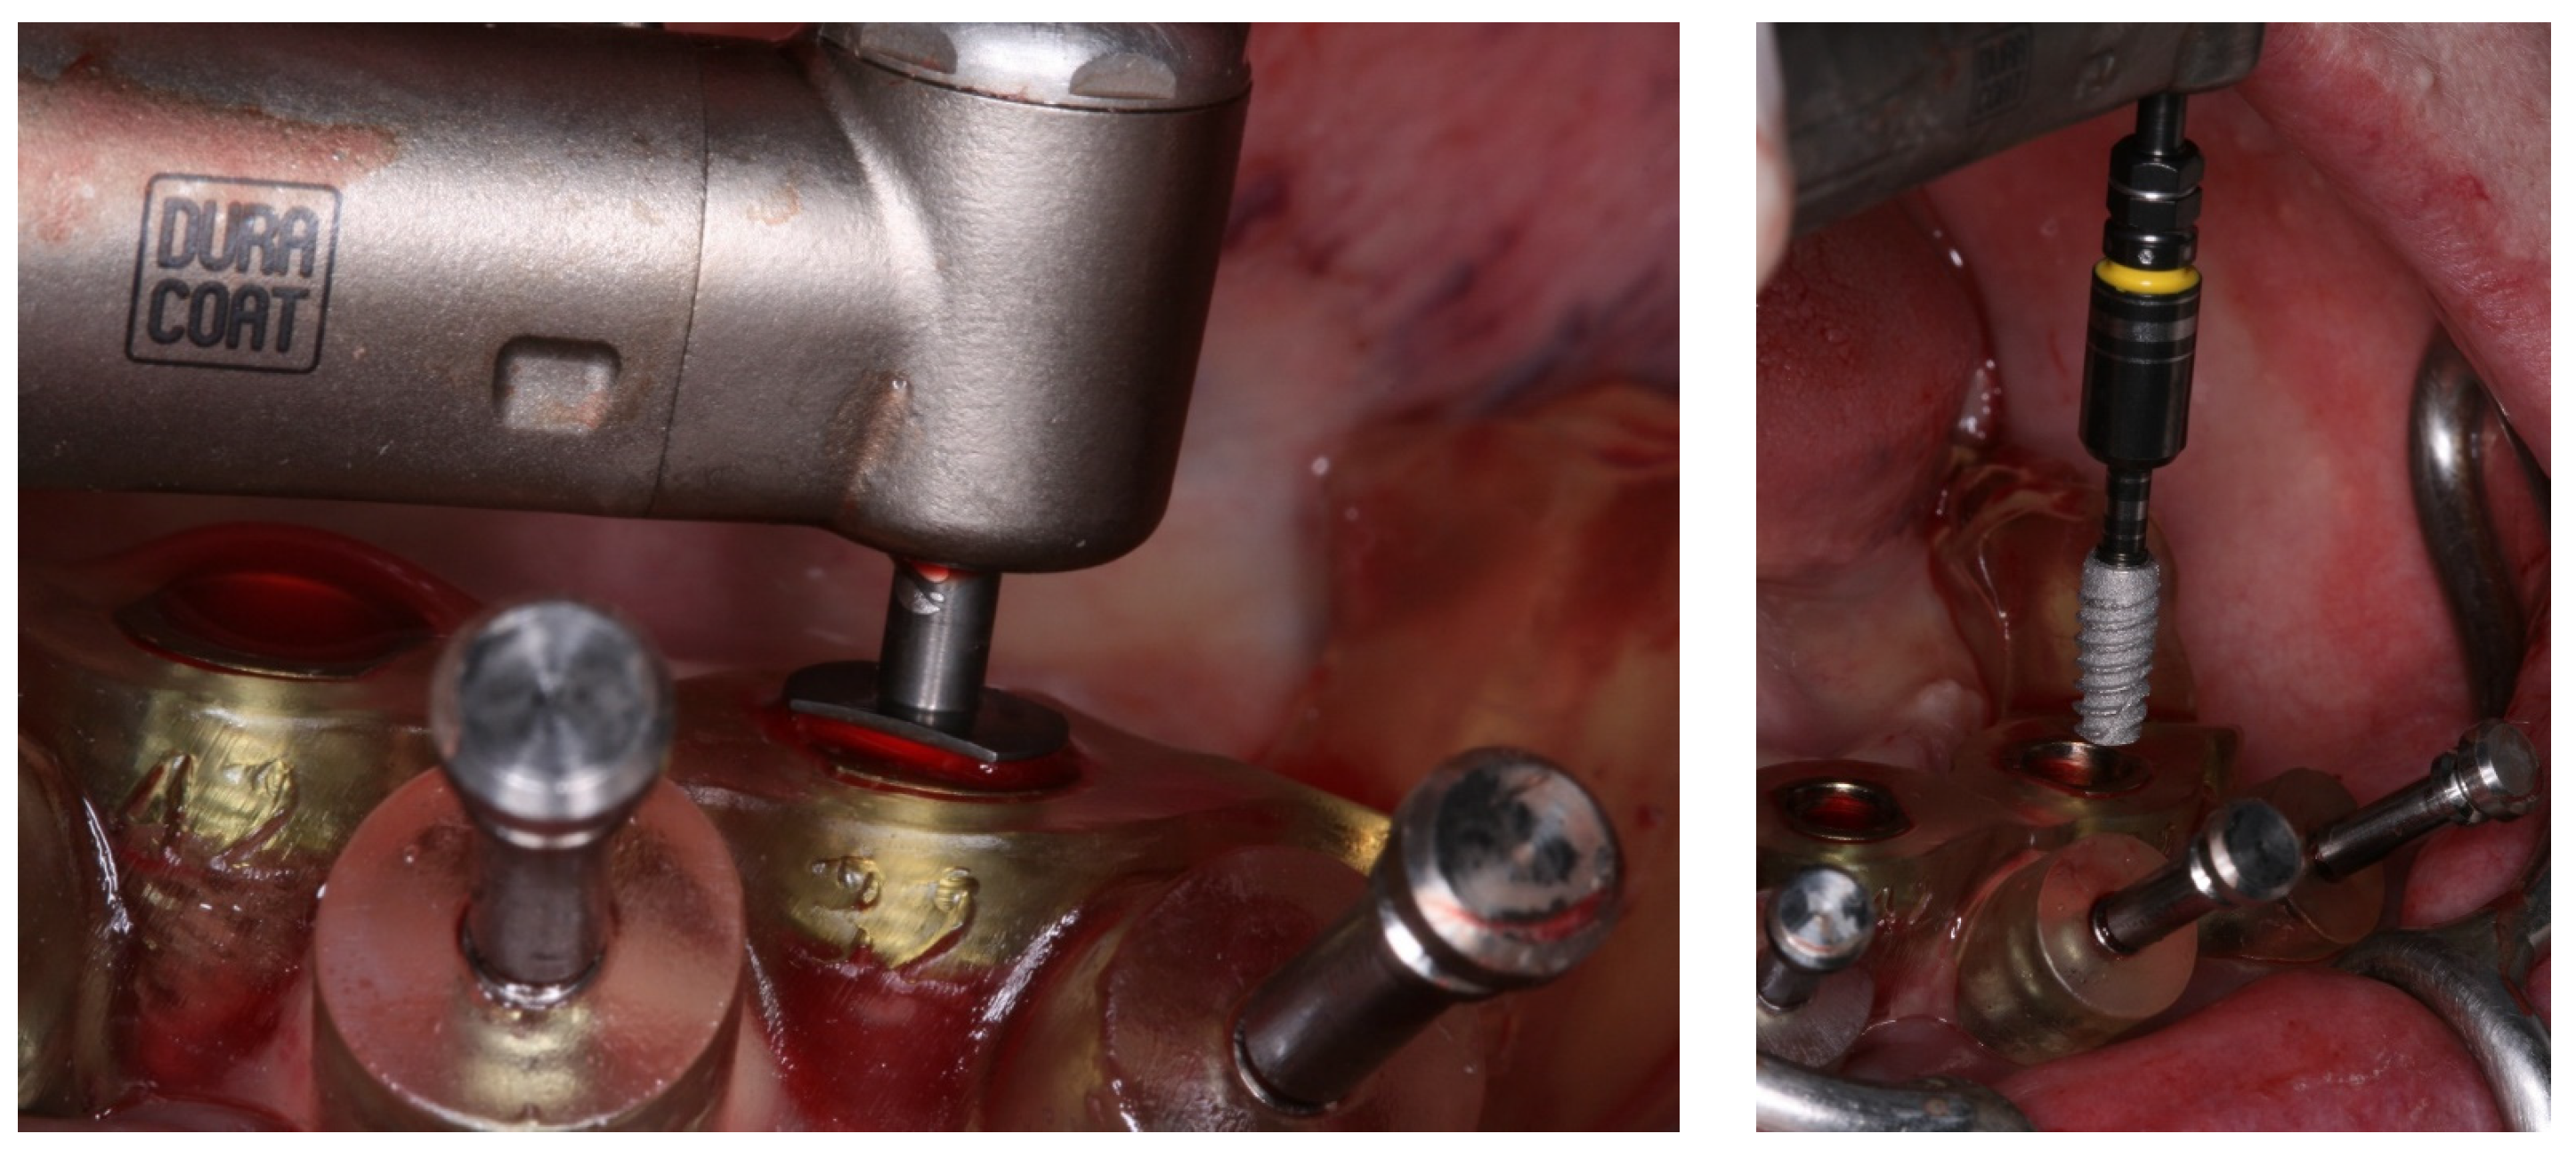

2. Case Report